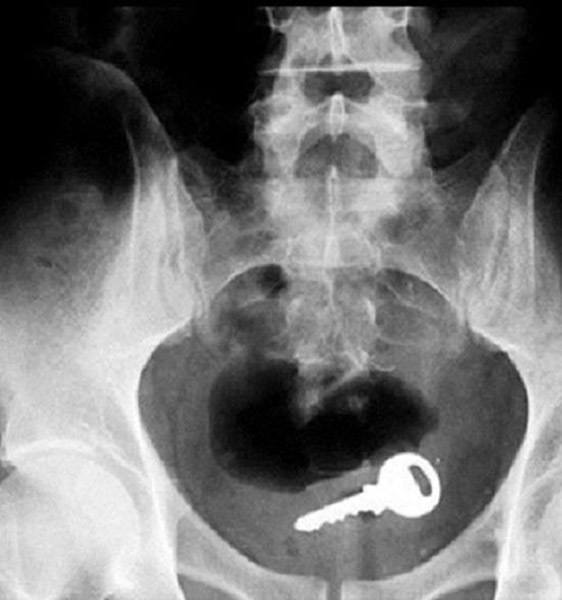

Röntgen filmlerinden "akıl almaz şeyler

Hastane koridorlarına düşenler bilir… Doktora görün, tahlilleri yaptır, röntgenleri çektir falan filan derken sayılmadan ömür gider. Gelin ki bu sefer ilginç şeyler çıkmış ki görün ağzımız açık kaldı…